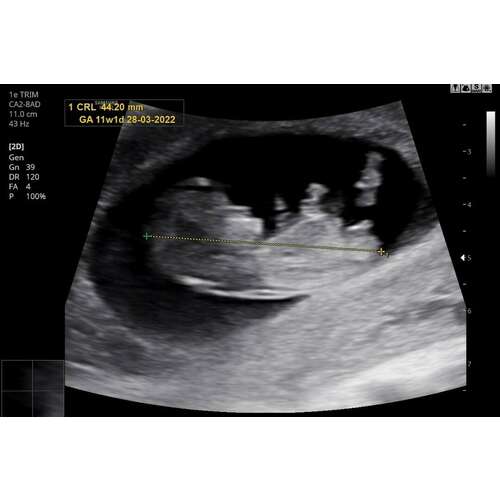

11+1 iemand een idee? 🤗💗💙